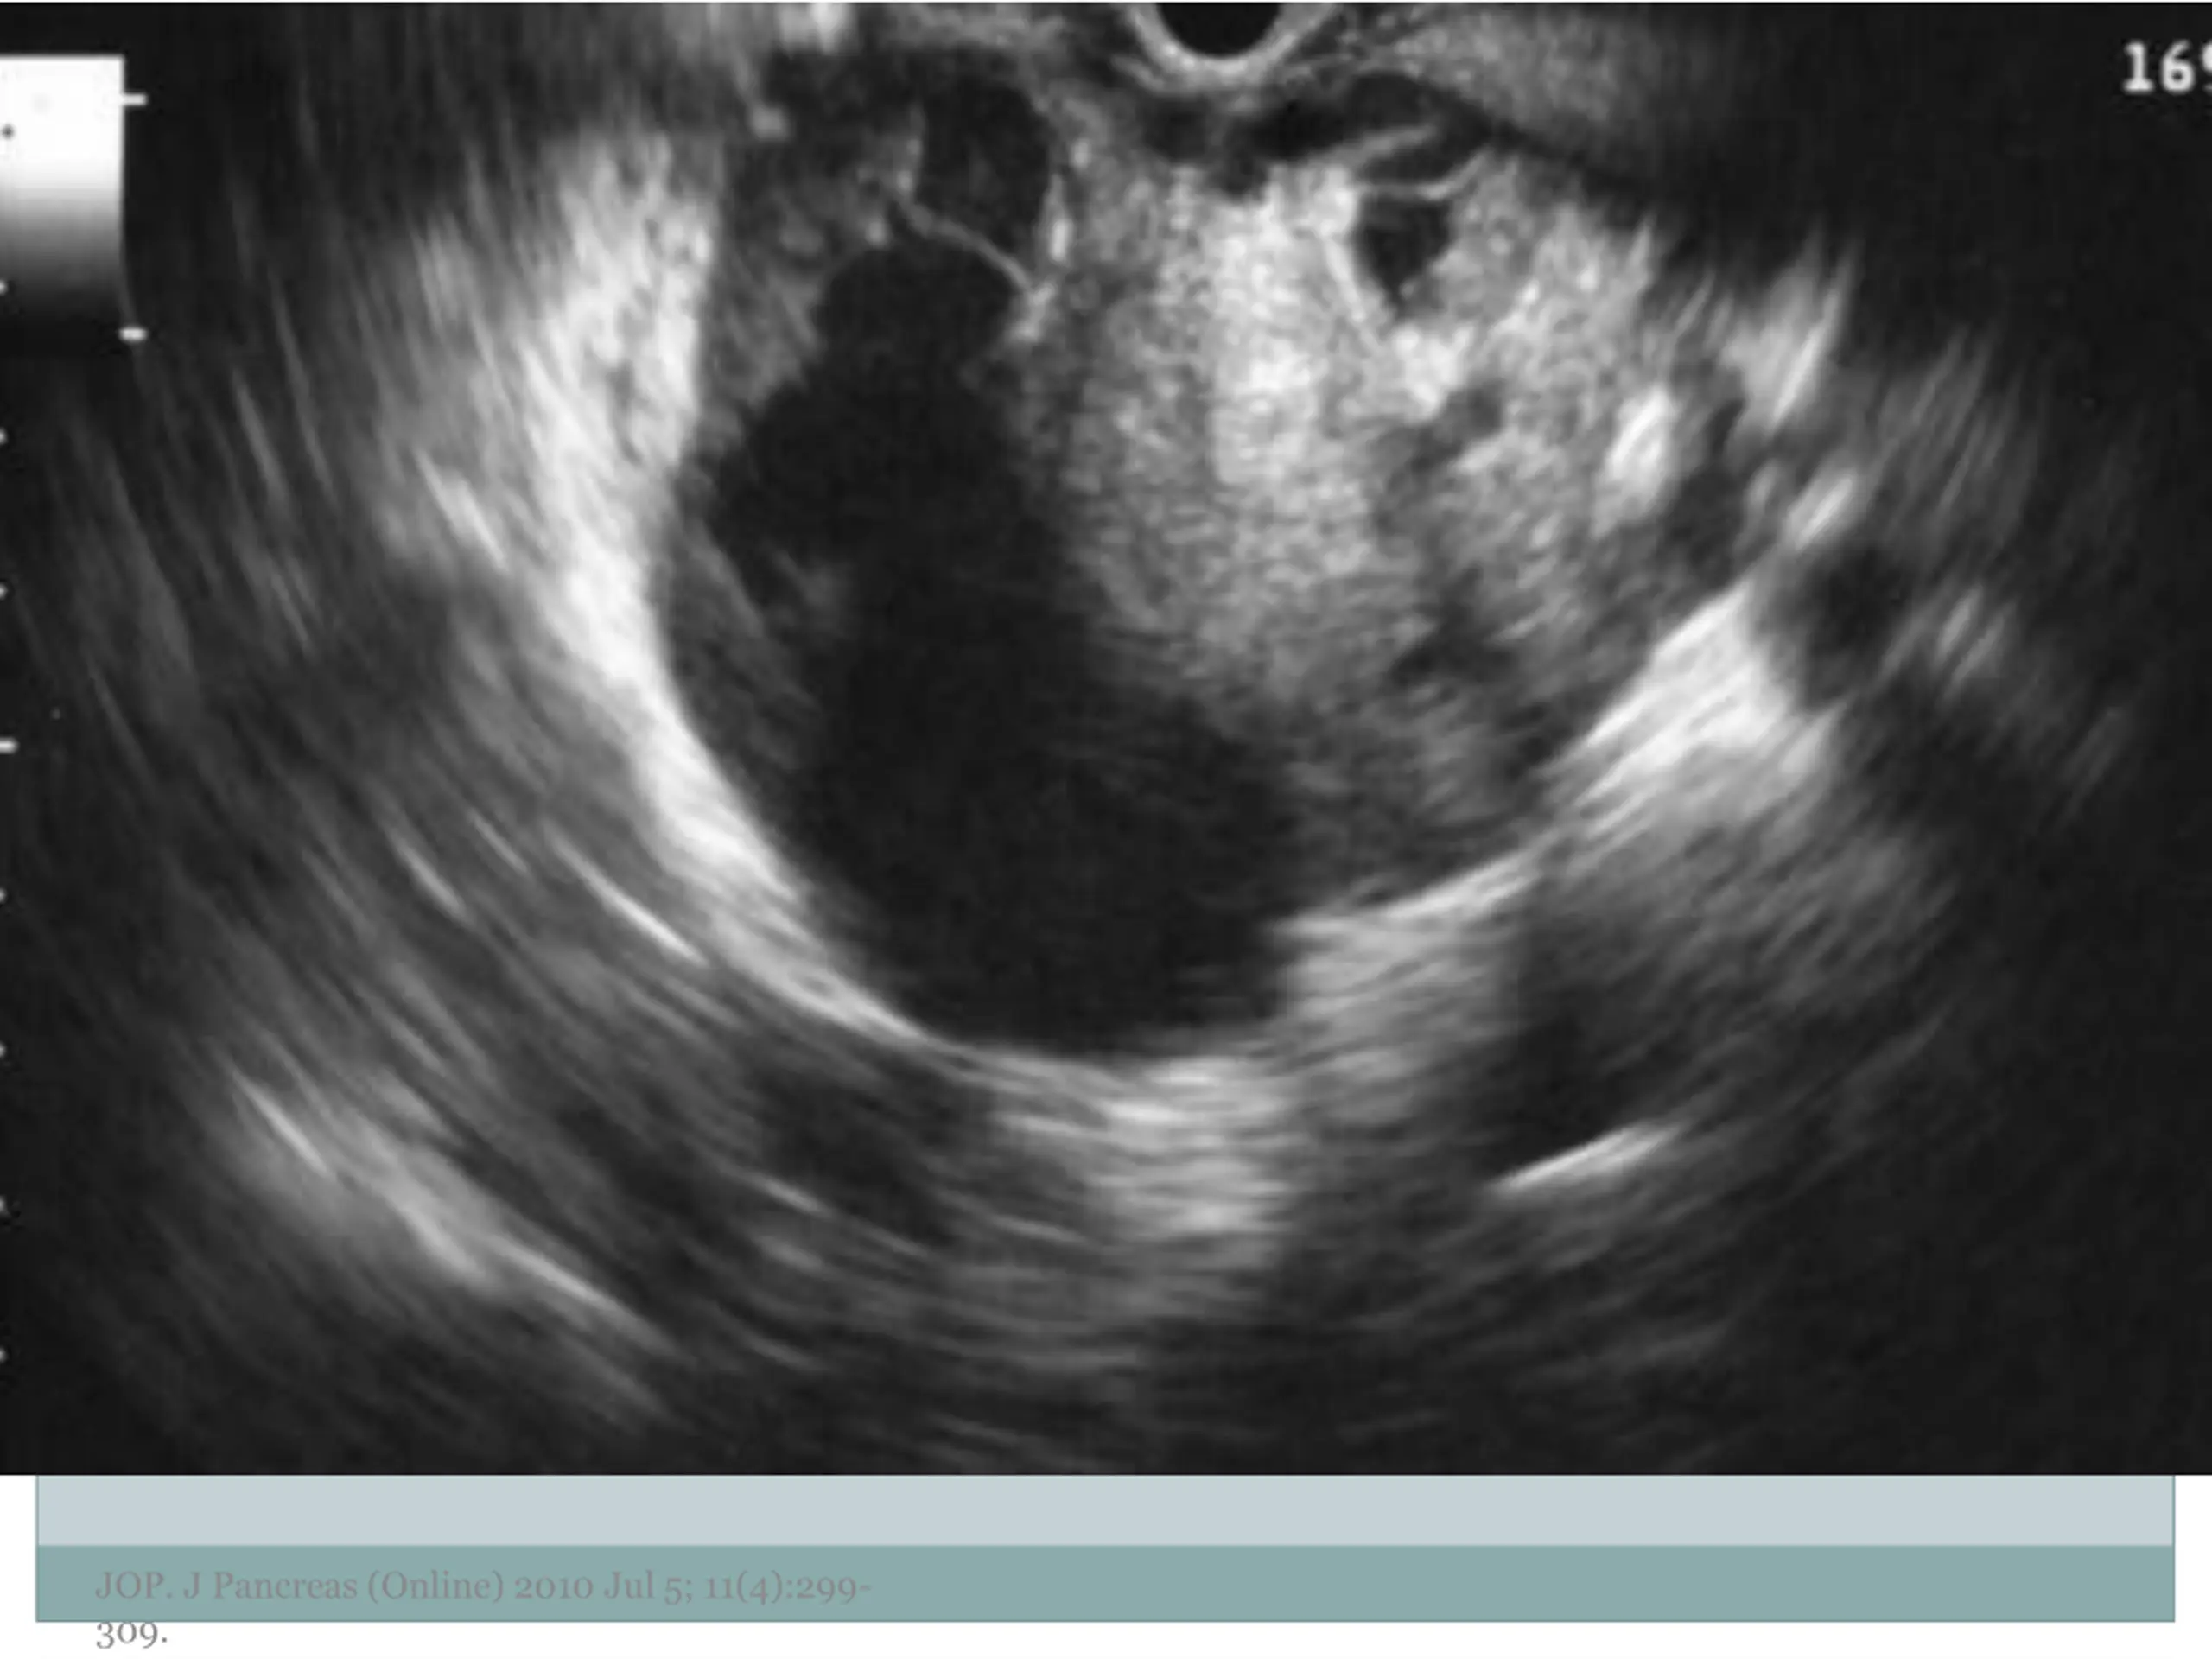

10. Examples of Morphology JOP. J Pancreas (Online) 2010 Jul 5; 11(4):299- 309.

11. JOP. J Pancreas (Online) 2010 Jul 5; 11(4):299- 309.

13. JOP. J Pancreas (Online) 2010 Jul 5; 11(4):299- 309.